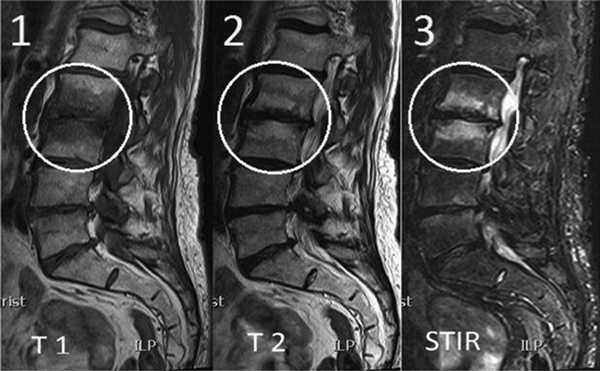

Изменения на МРТ по типу MCh1 характеризуются гипоинтенсивным сигналом на T1-взвешенных изображениях (ВИ), гиперинтенсивным — на Т2-ВИ и изображениях, полученных в Т2 с жироподавлением (T2-FS) или STIR режимах (рис. 1). Интенсивность сигнала увеличивается после введения гадолиния, эти МРТ-признаки соответствуют отеку костного мозга. Результаты микро-компьютерной томографии (микро-КТ) [11] и гистопатологического анализа [2, 12] демонстрируют разрушение и растрескивание КПП, ассоциированное с утолщением костных трабекул и увеличением числа остеобластов и остеокластов, поддерживающих повышенную активность ремоделирования кости. Также выявляется замена нормальной ткани костного мозга на богато васкуляризированную грануляционную ткань.

Рис. 1.ИзменениянаМРТпотипу MCh1. 1 — гипоинтенсивный сигнал на T1-ВИ; 2 — гиперинтенсивный сигнал на Т2-ВИ; 3 — гиперинтенсивный сигнал в режиме с подавлением сигнала от жира (STIR).